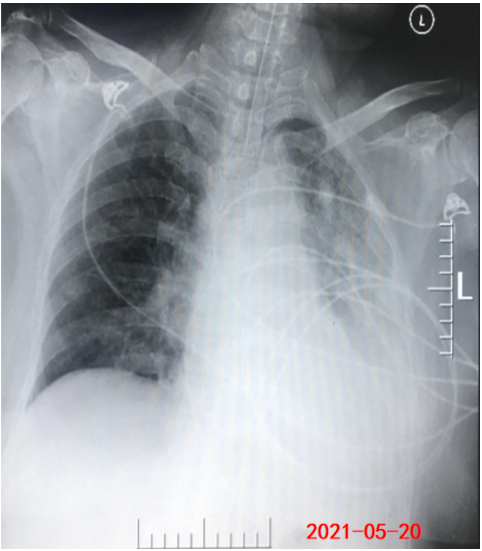

床旁胸片:左肺炎性病变;左下肺不张,左侧胸腔积液(图3)

图3  患者入我科后床旁胸片